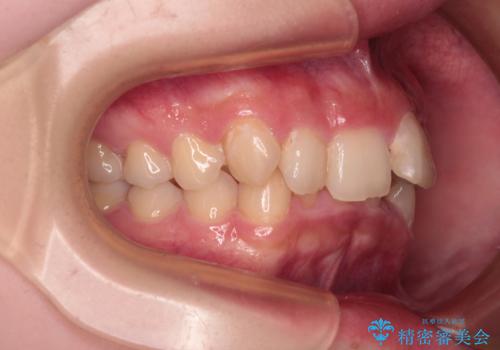

口元の突出感は気になっていないものの、デコボコを解消すると口元が前方に突出する可能性があるため、上下左右の第一小臼歯4本を抜歯して、ワイヤー装置にて矯正治療を行うこととしました。

下の前歯が隠れてしまうほど深く咬みこんでいたため、上顎前歯が前方に突出しているような印象がありましたが、咬み合わせが改善され、整った口元に仕上げることができました。